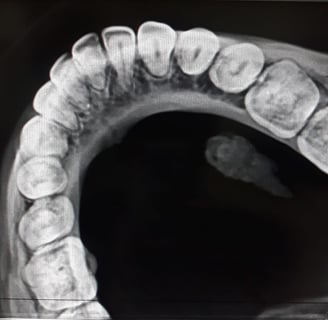

Radiografii occlusale

Radiografiile occlusale sunt utile pentru a evalua relația dintre dinți în timpul mușcării și pentru a depista probleme legate de alinierea dinților

Radiografiile occlusale sunt o formă specializată de imagistică dentară utilizată pentru a evalua relația dintre dinții superiori și cei inferiori în regiunea maxilară și mandibulară. Aceste radiografii sunt utile pentru a detecta probleme legate de alinierea și contactul dintre dinți, precum și pentru a identifica eventualele afecțiuni sau leziuni. În acest articol, vom explora radiografiile occlusale, tehnologia din spatele lor, beneficiile pe care le aduc și aplicațiile în îngrijirea dentară.

Radiografiile occlusale sunt proiectate să furnizeze imagini detaliate ale relației dintre dinții superiori și cei inferiori atunci când aceștia sunt în contact. Aceste radiografii se concentrează pe o zonă specifică și sunt utile pentru diagnosticarea și monitorizarea problemelor legate de occluzie, aliniere și contactul dintre dinți.

Radiografiile occlusale reprezintă o tehnică de imagistică dentală importantă pentru evaluarea relației dintre dinții superiori și cei inferiori, precum și pentru diagnosticarea problemelor de aliniere și occlusie. Cu ajutorul acestor imagini detaliate, profesioniștii din domeniul stomatologiei pot oferi îngrijire dentară de calitate și pot planifica tratamente adecvate pentru pacienții lor.